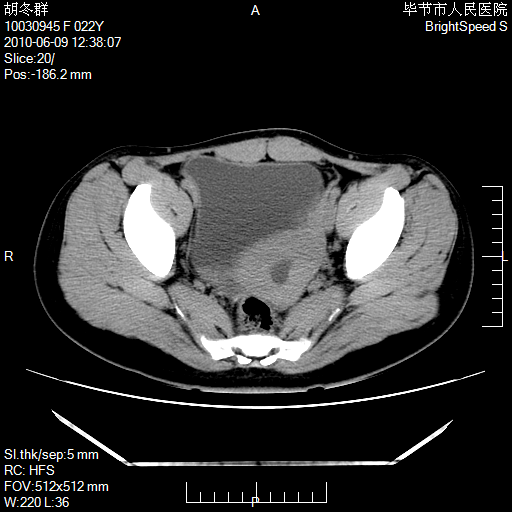

患者23岁,发现腹部包块3月。

左侧卵巢囊腺瘤或囊腺癌

盆腔内囊性占位性病变;考虑左侧卵巢囊腺瘤。

有分隔、壁薄,支持考虑左侧卵巢囊腺瘤。

左侧卵巢浆液性囊腺瘤。

支持考虑左侧卵巢囊腺瘤;宫腔积液。

有分隔、壁薄,支持考虑左侧卵巢囊腺瘤。排尿后,膀胱缩小,由于重力作用,肿块下移就到了膀胱位置,很好理解。